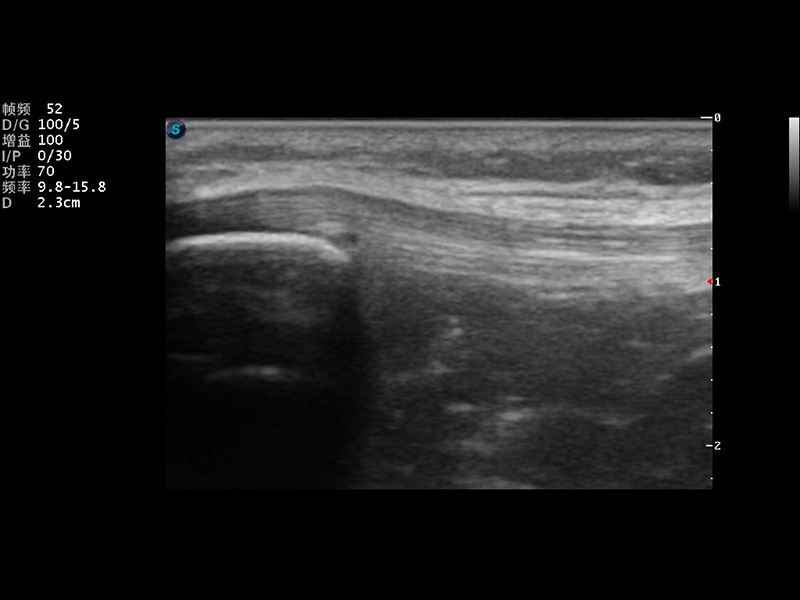

S9便携式彩色多普勒超声诊断仪是环球UG官网研发的高端便携彩超设备,外观设计新颖、产品性能卓越。S9在便携超声领域采用了突破传统的触摸屏交互设计,并以先进的软件硬件技术和设计理念,为您带来清晰的图像质量、稳定的工作性能和便捷的操作体验。